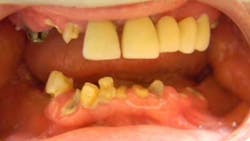

"Kevin started having terrible trouble with his teeth," says Cindy. "He was in pain, and then his teeth started breaking off at the gumline. And it's my understanding that it's from the inhalers, which just eat at the teeth. He's on three different ones and a nebulizer every day, so it just ate them away."

"When Kevin and Cindy first walked in, it broke my heart to see him in such pain and agony. It was tough for him to smile and for him to eat as well," says Dr. Mansour. "And he's such a brave soul. For him to go through that just really broke our hearts. We knew with modern dentistry, with modern medicine, and a great patient and a great team, we could fix this."

Dr. Mansour began a two-month-long treatment plan to restore Kevin's smile. When asked if he was nervous about undergoing dental treatment, Kevin says not at all. "His whole office, all the people who work for him, are just absolutely marvelous. He was above and beyond anything I expected from a dentist."